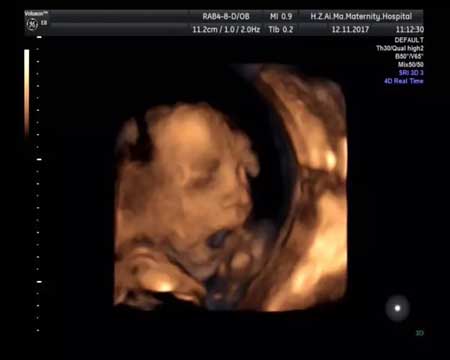

上面这些,都是在中孕期的超声影像筛查时看到的哦~

中孕期的超声影像,除了让宝妈们看到胎宝宝在宫内的表情,它更重要的一个任务是:对胎宝宝的结构畸形进行筛查!